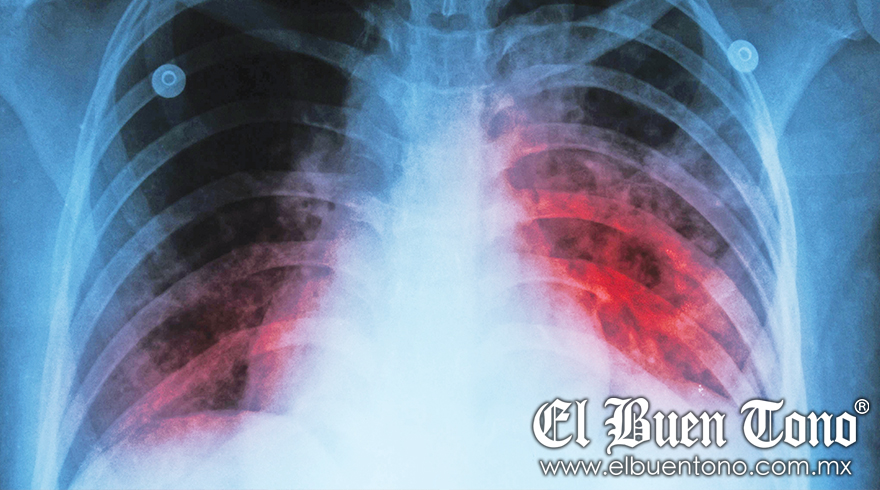

“Eso predispone de una forma importante a las personas a la tuberculosis”. Asimismo, el médico explicó que la tuberculosis es una enfermedad infecciosa, una bacteria que casi siempre afecta a los pulmones.

Asimismo, añadió que el 80% de los casos de tuberculosis se da en el pulmón, donde los síntomas son los siguientes: Una tos con flema, en ocasiones con sangre, febrícula.